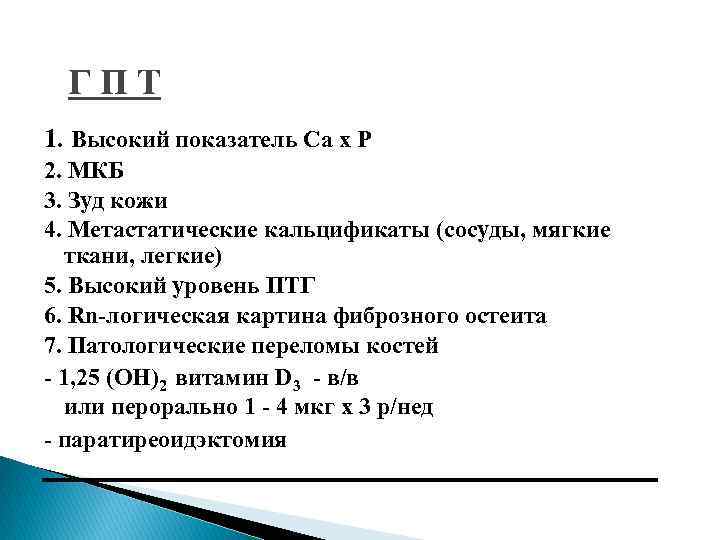

Код мкб 10 атерома головы

Код мкб 10 атерома головы 109 фото